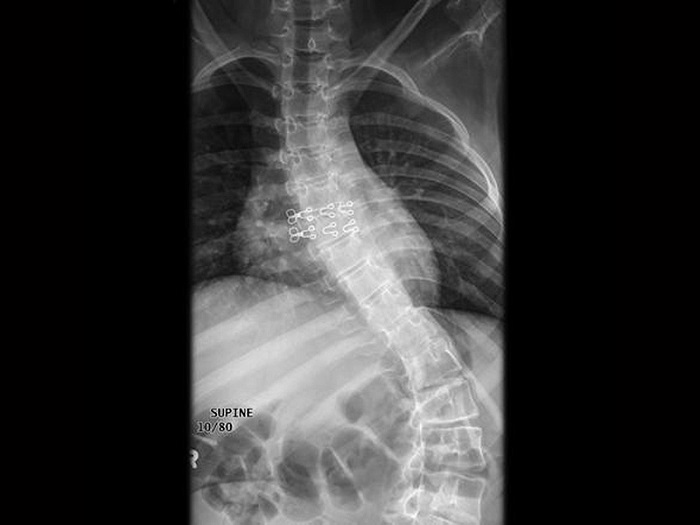

- деформация костного отдела (выворачивание тазобедренного сустава, развитие сколиоза, и возможно, формирование «куриной» грудной клетки);

- сколиоз;

- деформация грудной клетки;